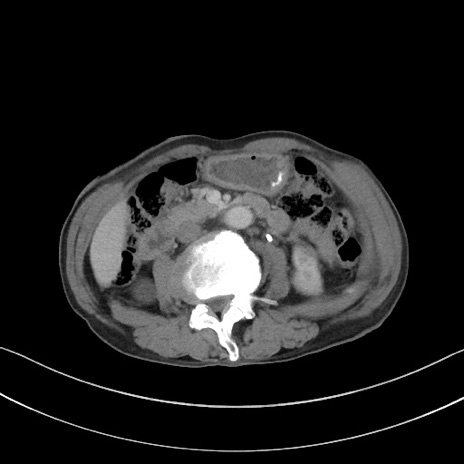

症例3(横断像)

【症例】 70歳代男性

【主訴】右鼠径部腫瘤、疼痛

【現病歴】本日朝より上記主訴あり、受診。

【既往歴】膀胱癌にて膀胱全摘、両側尿管皮膚瘻

【データ】WBC 5600、CRP 0.56